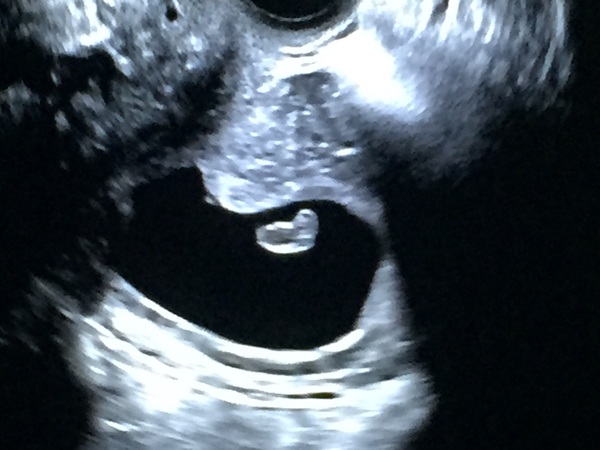

Ok, so something weird has happened. I had to go for a Rescan today after over a week of pain and bleeding and mourning my lost baby. I even believed I'd passed the sac this morning when I found a jelly-like grey blob.

Strangely, at the scan the sac has grown and and after nothing being seen on the original scan a week ago, we now have a foetus measuring 6wks 4days. I should be 11weeks according to my BFP and last period.

The sonographer saw a heartbeat briefly then couldn't find it again. We saw it for a second time for a tiny moment and then it was gone. I need another scan next week to see if it really is still a viable pregnancy or not.

I'm not getter my hopes up too high but here's the scan